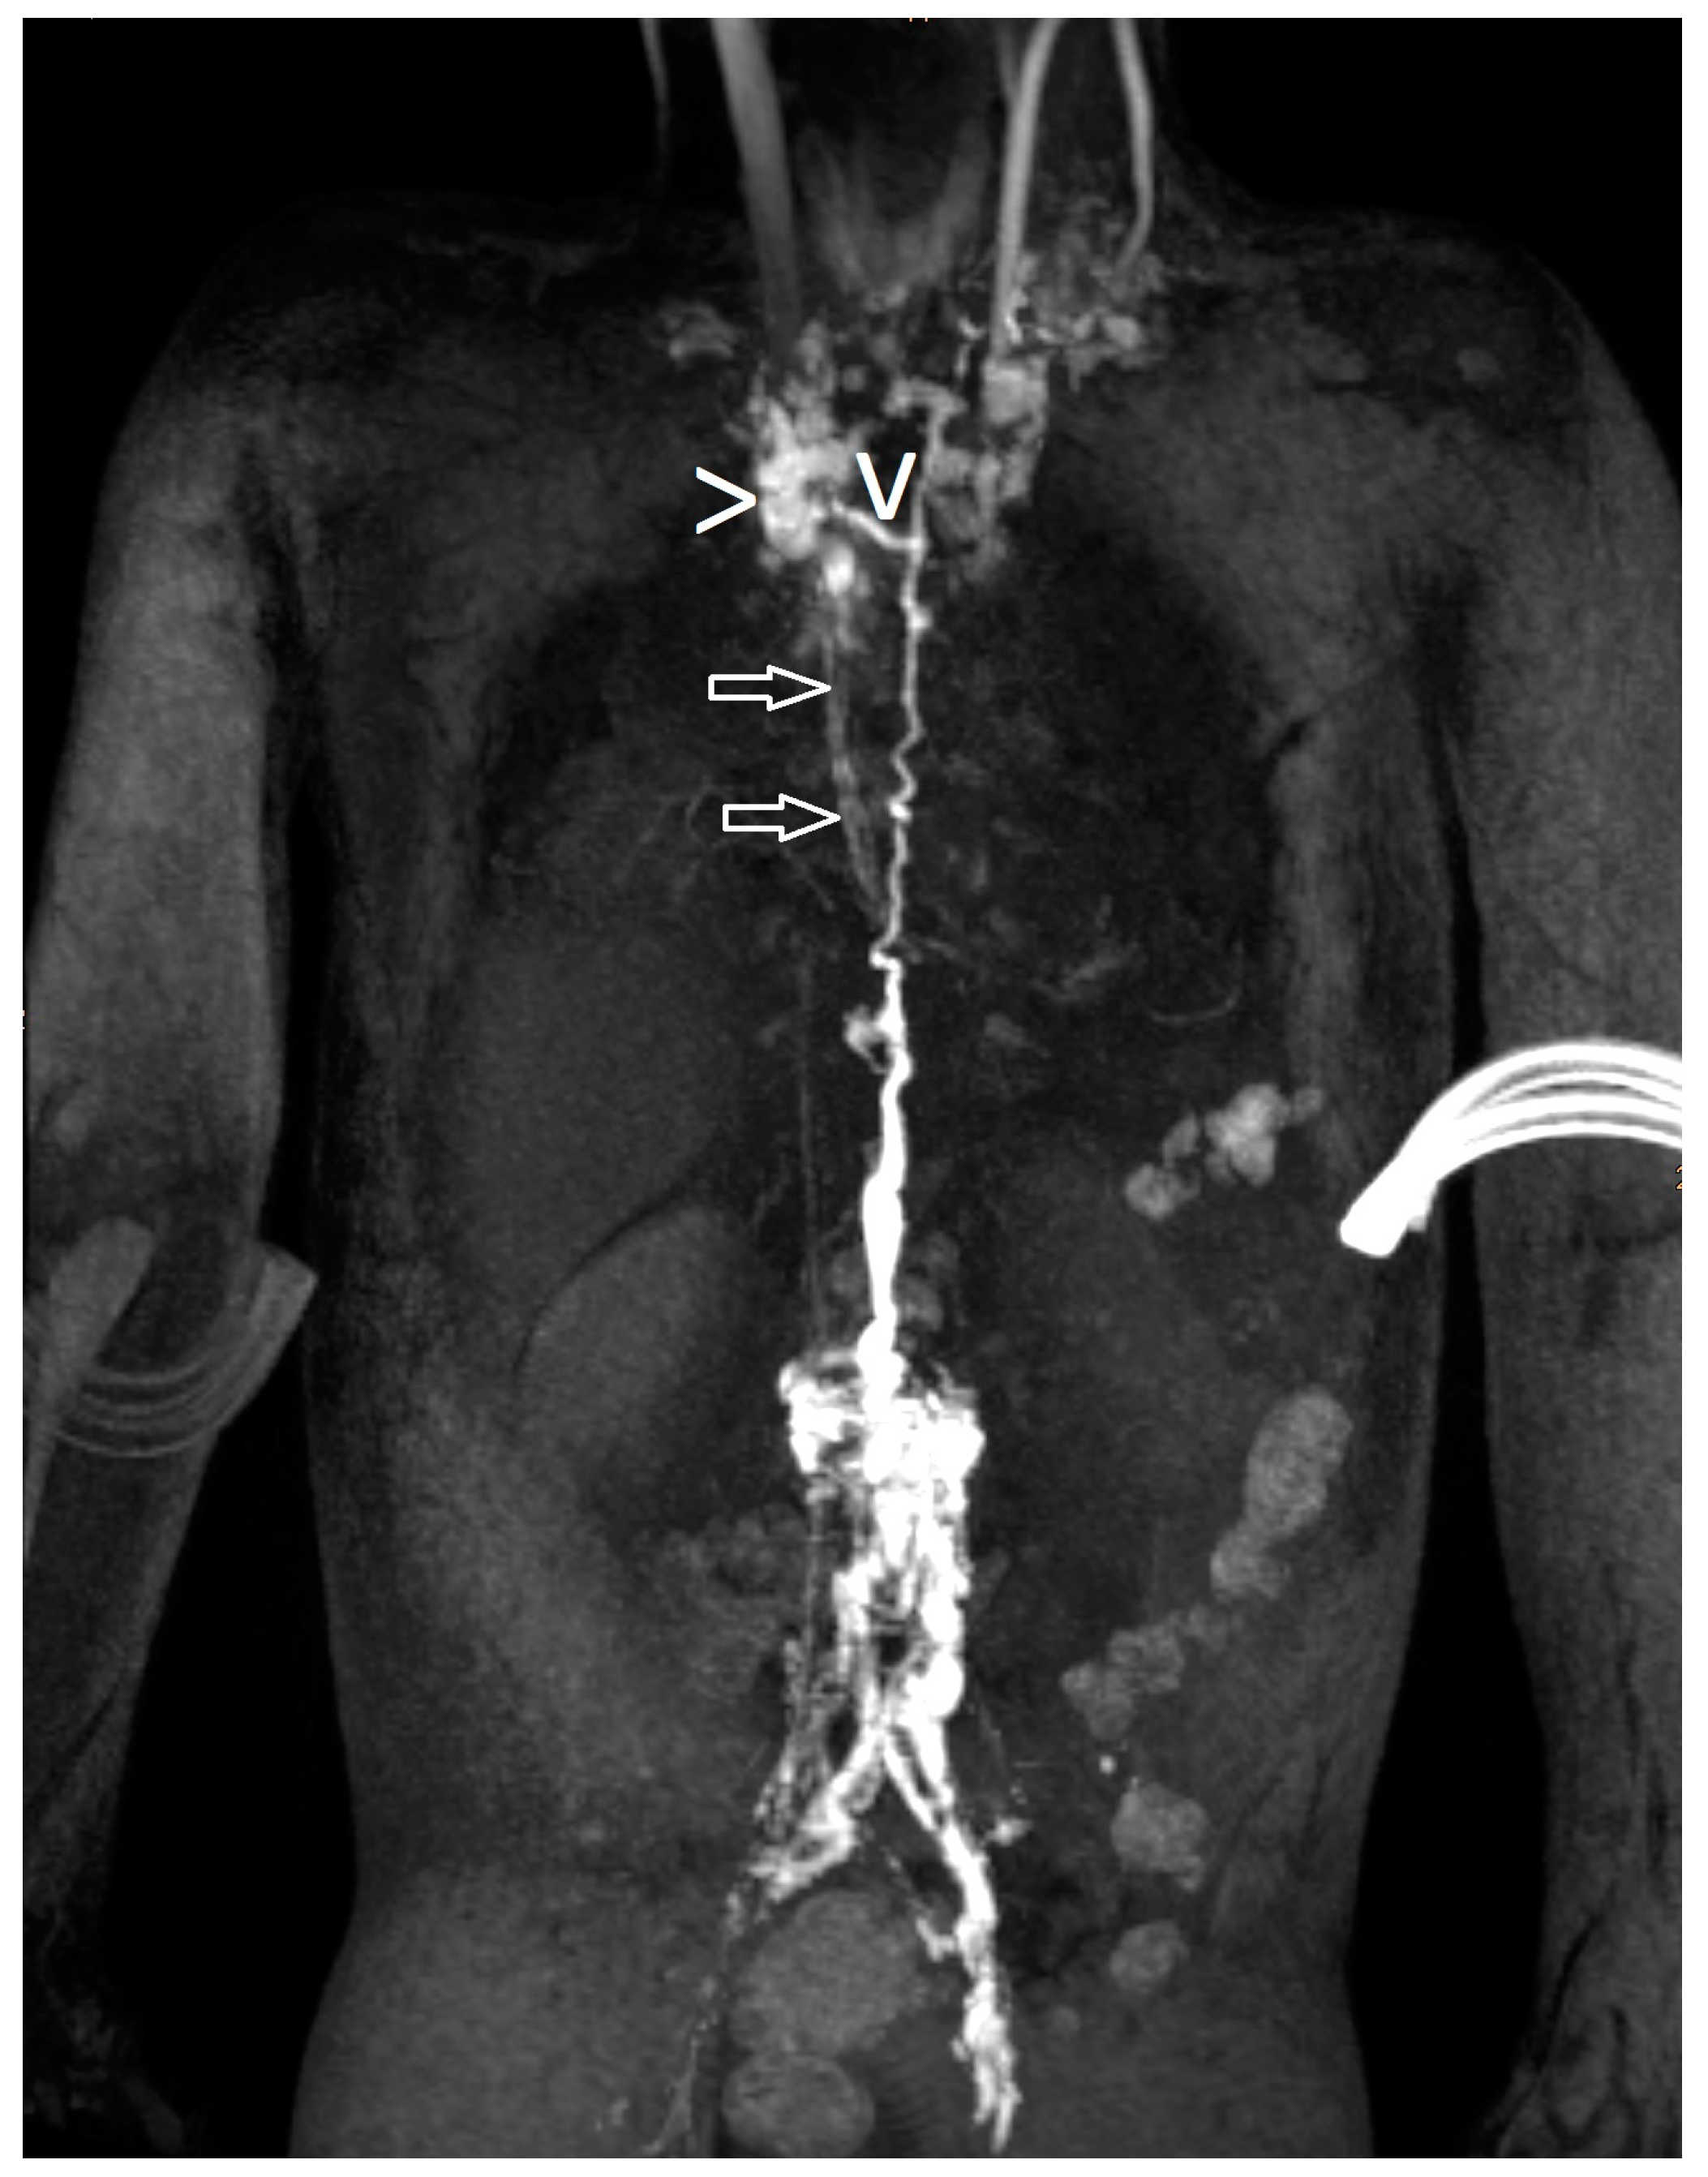

| 21 | 4 | increased signal mediastinum, hilum, lung le > ri | retrograde flow from TD with diffuse mediastinal and peribronchial perfusion | thoracic vertebrae 4–10 to left mediastinum | MCT diet, macitentan, alteplase inhalation, salbutamol, diuretics | glue embolization of TD | cast free after intervention (FU 1 a 4 m) tapering off sildenafil |

| 22 | 4 | increased signal (mediastinum), hilum/lung ri | retrograde lymphatic flow to mediastinum and lung parenchyma ri | from hilum to ri lung | fat reduced diet, sildenafil, alteplase/ fluticasone inhalation | selective glue embolization of 2 branches of TD | cast free after intervention (FU 4 a), cessation of fat-reduced diet, |

| 23 | 4 | increased signal mediastinum, hilum, lung ri > le | retrograde lymphatic flow towards lung parenchyma & mediastinum ri > le and peribronchial perfusion | fistula visualized | fat reduced diet, sildenafil, diuretics, alteplase inhalation, azithromycine | selective glue embolization of fistulas | cast free after intervention (FU 1 a 4 m) |

| 24 | 4 | increased signal at the mediastinum and hilum bilateral | retrograde lymphatic flow towards mediastinum and hilum bilaterally | no fistula visualized | diuretics salbutamol inhalation. Budesonide | TD decompression | cast free after OP, albumin normalized (FU 3 a 5 m) |

| 25 | 4 | increased signal neck, axilla, mediastinum, hilum, lung ri, fistula from liver to ri lung | little contrast | no fistula visualized | lisinopril, diuretics, spironolactone, bisoprolol, sildenafil, diuretics, alteplase inhalation. | not performed yet | still casts |

| 26 | 4 | increased signal neck, axilla, mediastinum, hilum, lung | retrograde lymphatic flow towards mediastinum, hilum and lung parenchyma with peribronchial perfusion ri | from hilum to ri lung | spironolactone, sildenafil, diuretics, alteplase inhalation, hydrochlorothiazide | not performed yet | still casts |